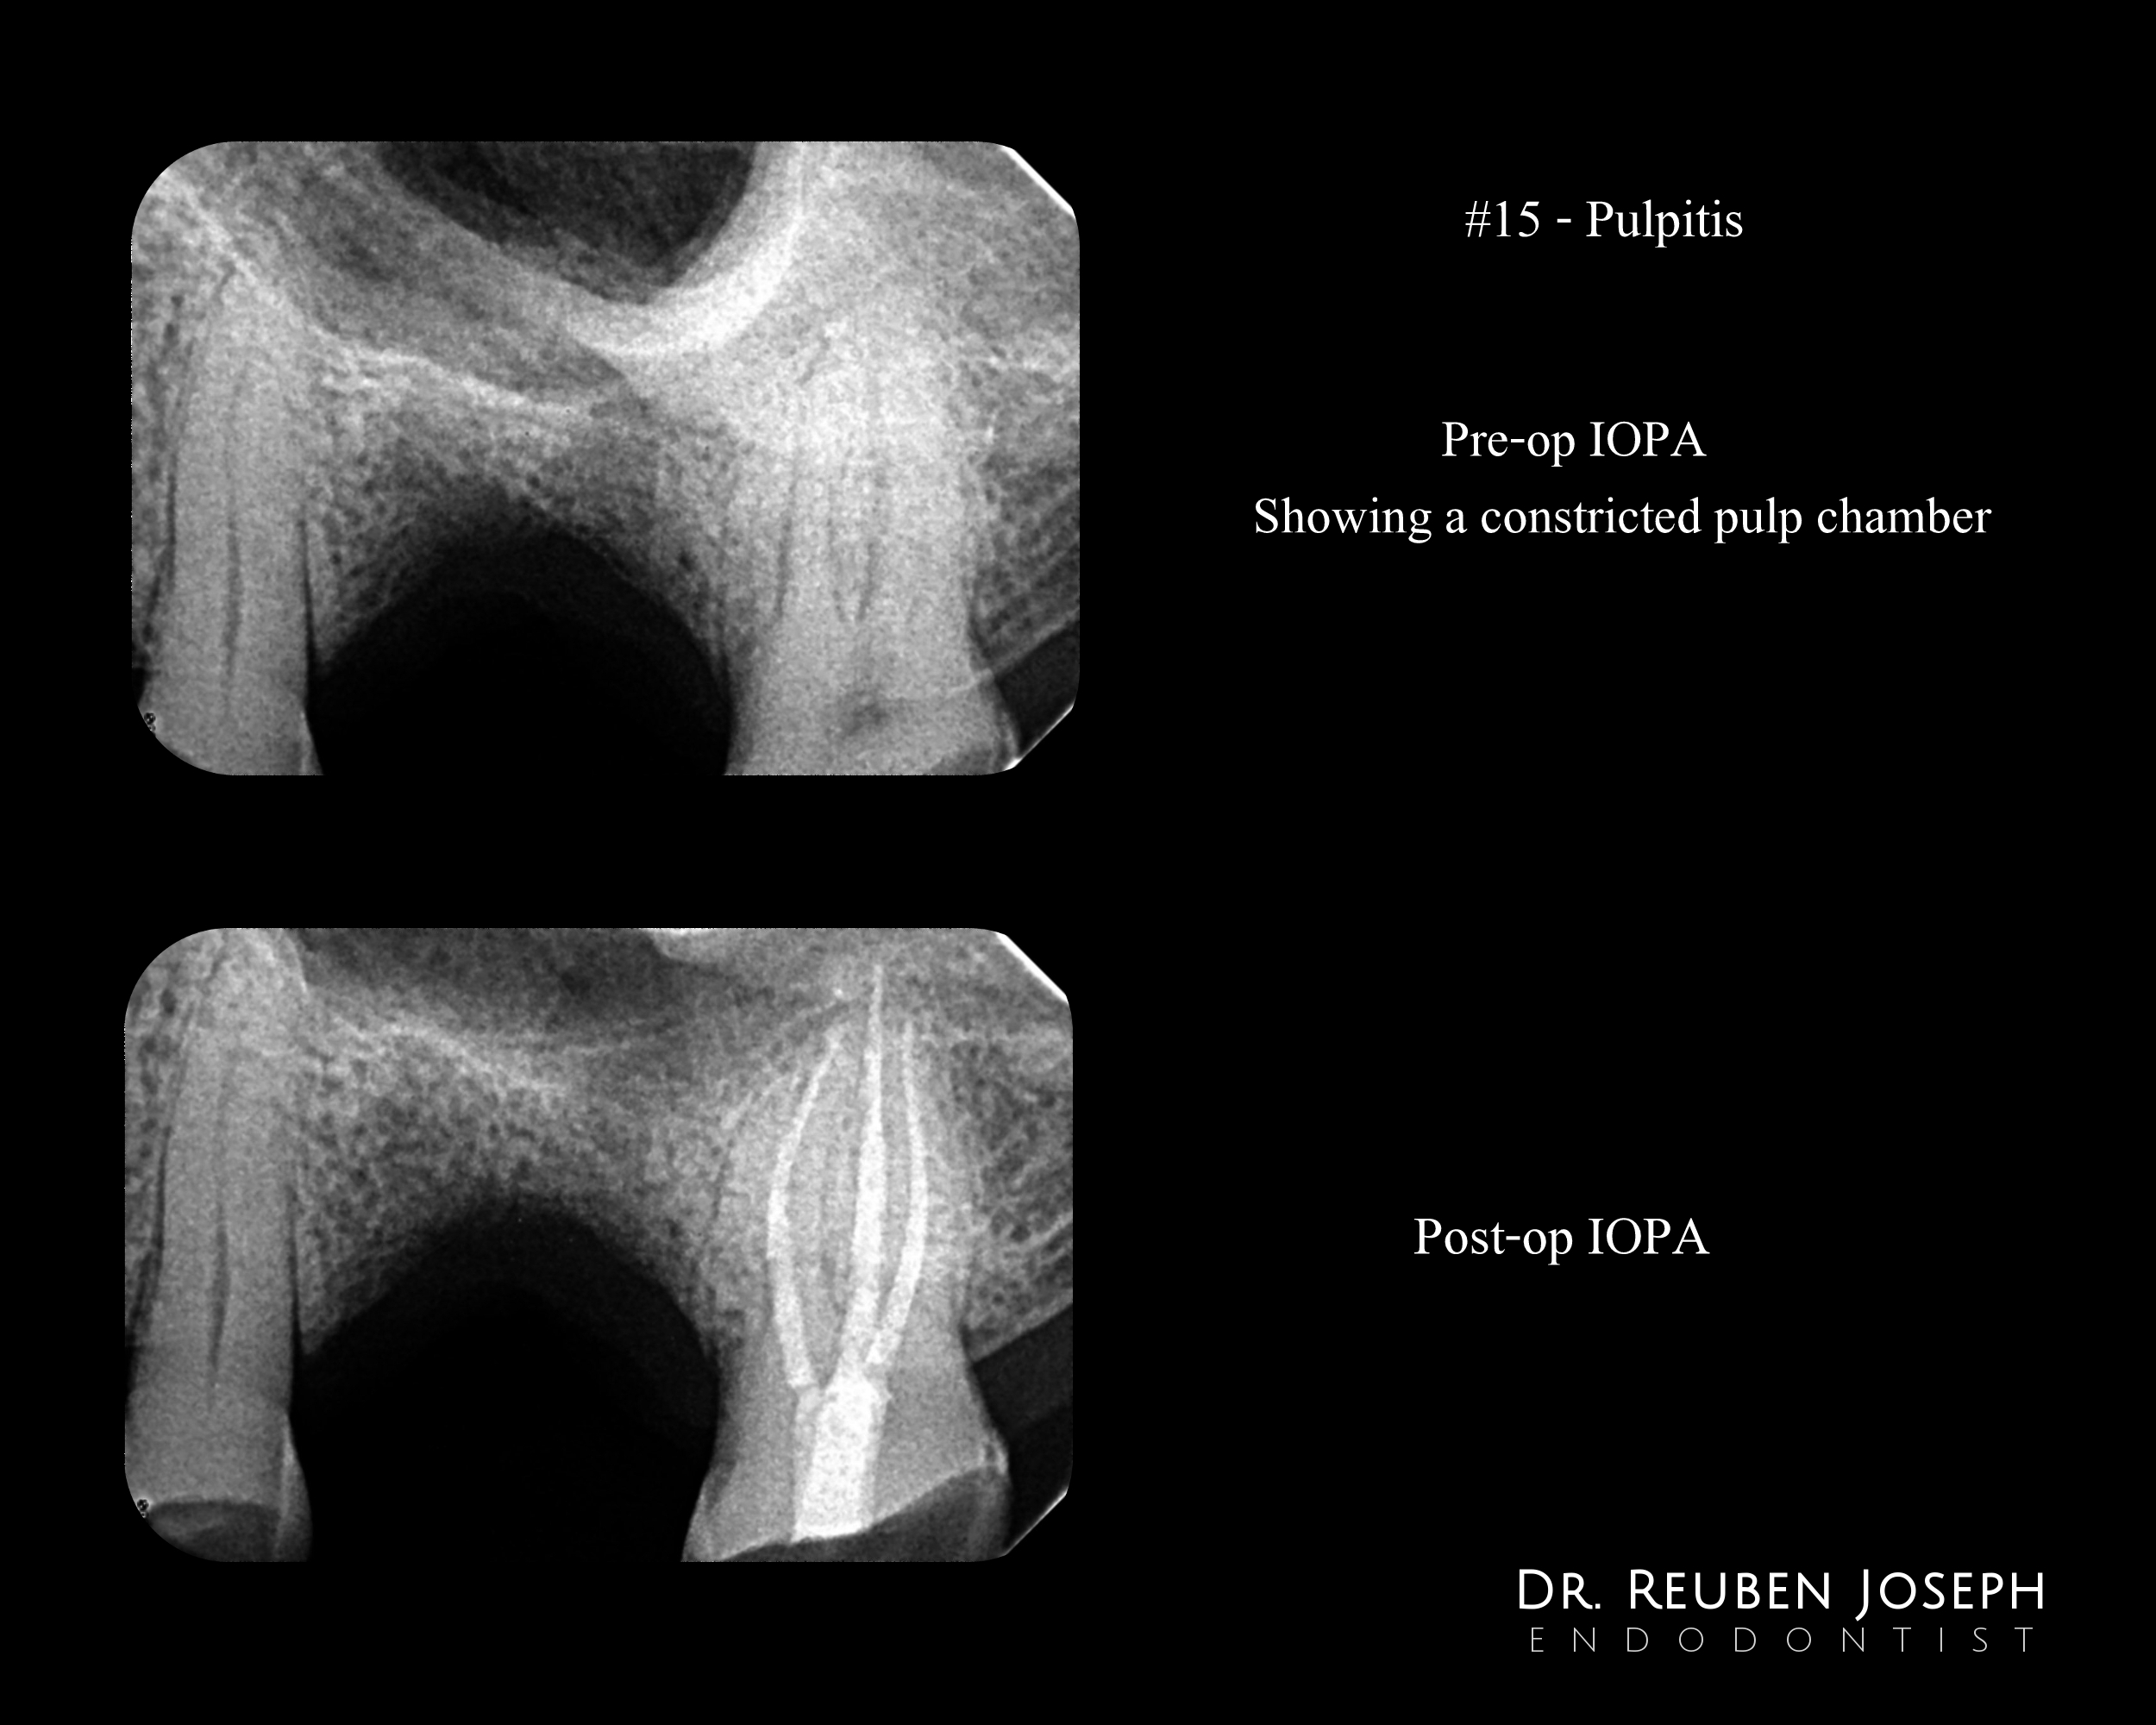

Access cavity planned taking into account the regression of the pulp chamber size. Canals shaped through the angles the canals project centrally.

determining the best place of entry to reduce additional damage to the tooth structure driving directions. Ensuring that the access allows for adequate visibility and instrument maneuverability within the constricted chamber.